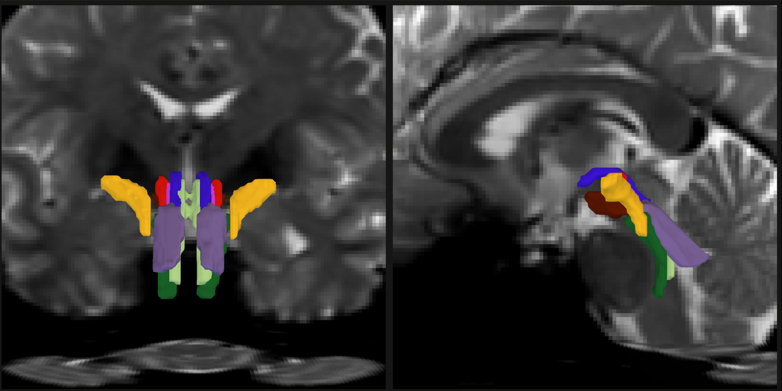

In two panels there are face-on and side-view cross sections of a human brain in pixellated gray. In the bottom center of each image color-coded crescent shapes delineate discrete nerve fiber bundles.

Researchers have developed a new way to resolve distinct bundles of nerve fibers in the brainstem. In this detail of a figure from the paper offering two different cross-section views of a human brain, individual bundles are segmented and color-coded.

Image: Mark Olchanyi/Emery Brown Lab